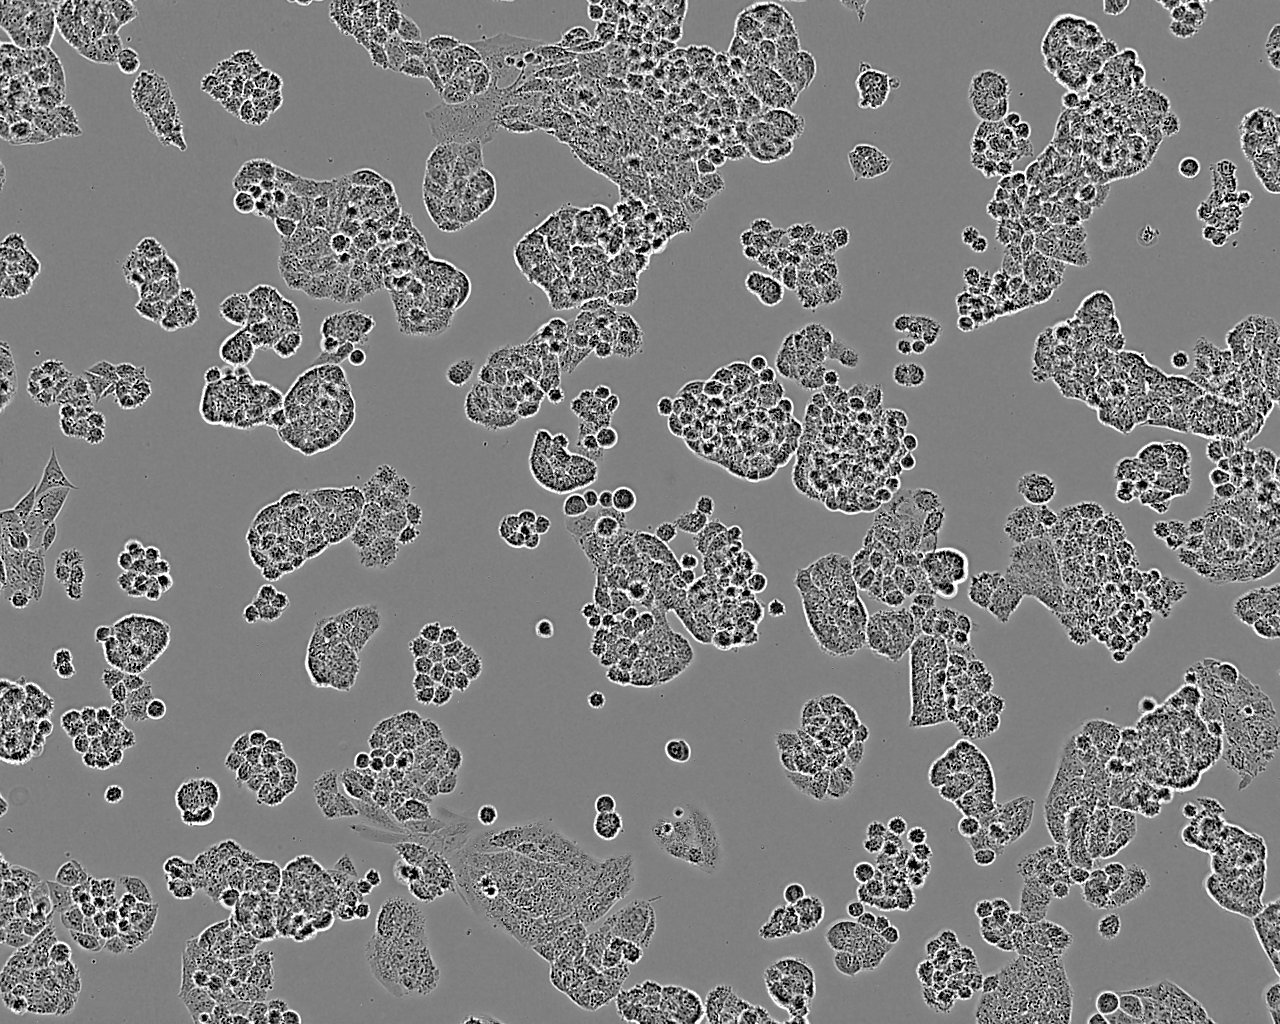

细胞名称: A2780细胞, 人卵巢癌细胞

细胞又名: A-2780; 2780; A2780S

细胞来源: ECACC

产品货号: 93112519

组织来源: 卵巢

疾病特征: 卵巢癌

细胞形态: 上皮细胞样

生长特性: 贴壁生长

细胞图片: A2780细胞图片

A2780细胞图片